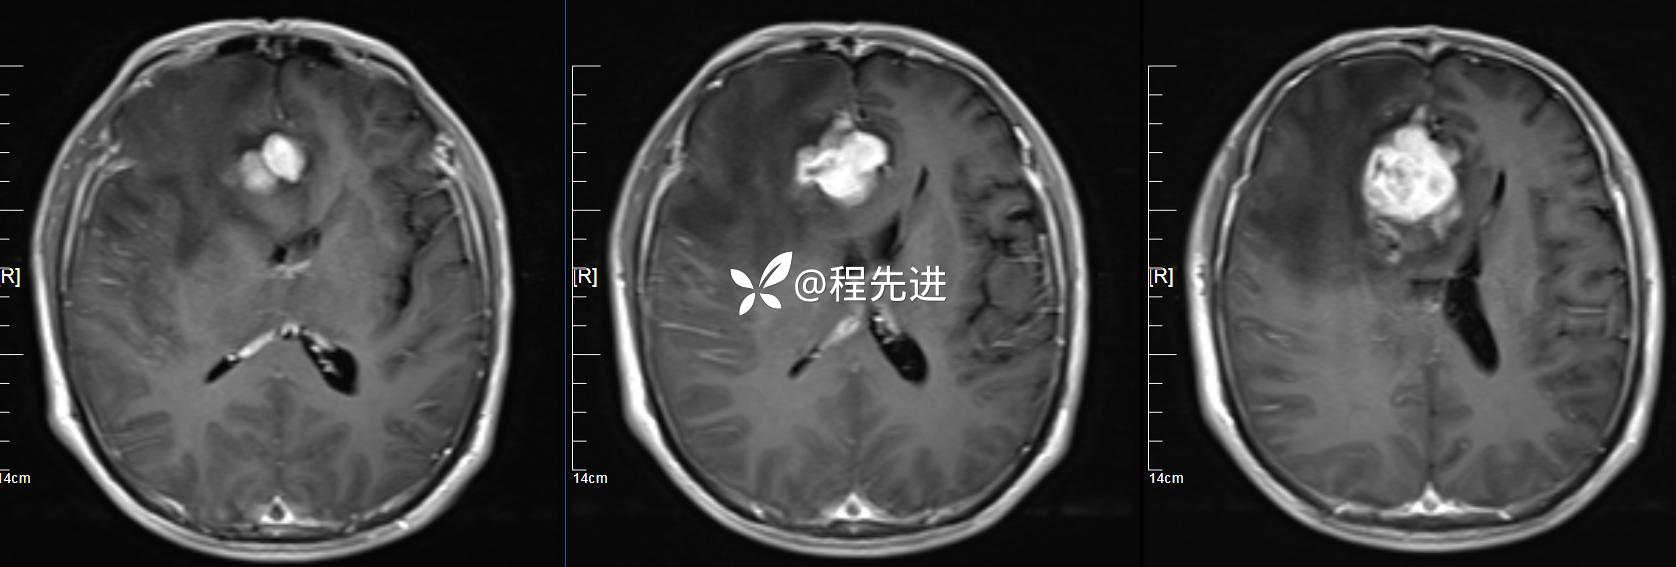

MRI增强: